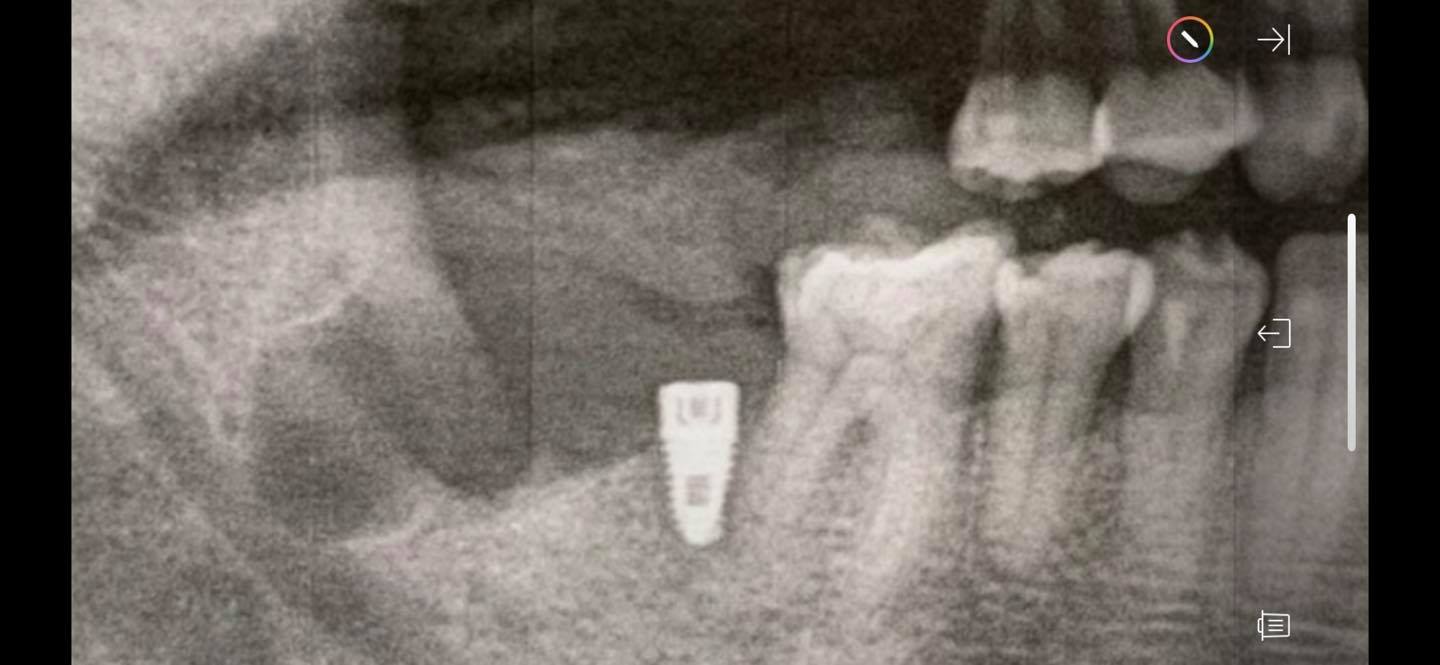

牙醫建議我到醫學中心的口腔外科做全身麻醉,拔拔看。但透過關係,找到一位經驗豐富的台灣牙醫教授要幫我拔,但他需要我回台灣後,拉鋼線,把智齒牽引在前面的植體上,三個月後,等拉出來一些,再拔,這樣比較不會傷到下面的三叉神經(否則傷到就半邊嘴唇永遠麻麻的,無知覺,一輩子喔!)。

但我真的等不下去了,因為這顆爛智齒已經影響到前面的植體和臼齒了!

我實在不想全麻,終於加州的這位台裔牙醫看過我的X光片後,說不用全麻,而且大概花十分鐘可以拔起來。